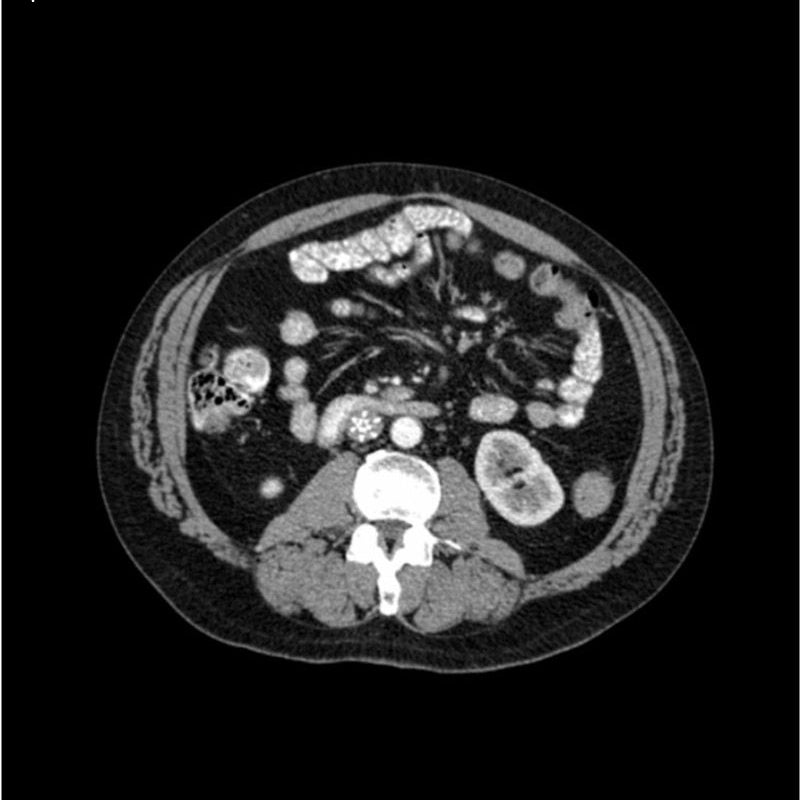

abdomen in portal venous phase. It covers the tenth thoracic vertebra to the third lumbar vertebra. The phantom represents an abdomen after cholecystectomy with small clips. The liver has typical signs of cirrhosis and there is an inferior vena cava filter implanted at the level of the third lumbar vertebra. Both kidneys have cystic lesions and there is a small kidney stone on the left side.

Realistic simulation of vasculature, bone and soft tissues, including the liver, pancreas, spleen, adrenals, kidneys, stomach, small intestine and colon.

- Liver cirrhosis

- cholecystectomy

- inferior vena cava filter

- kidney cysts

- kidney stone

- lymph nodes.